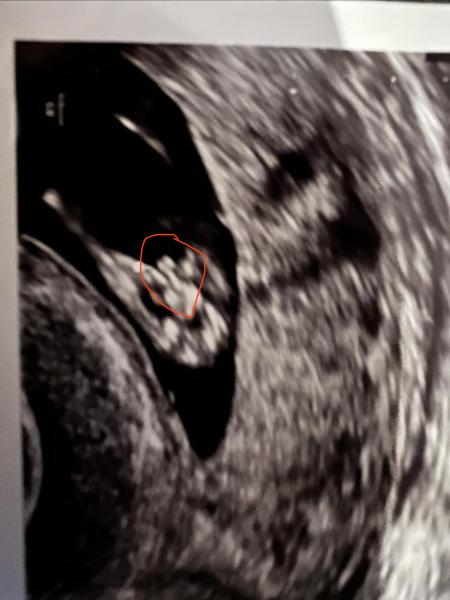

Habe aber nun eine Frage an euch. Bin bei 11+4, also 12. Woche. Heute beim US hat meine FA die Tendenz “eher Mädchen” geäußert. Hat es mit einem Pfeil sogar extra gekennzeichnet. Als ich mir dann zu Hause das Bild genauer angeschaut habe, sah es dann irgendwie doch nach einem Jungen aus

oder sieht es in der 12. Wochen bei beiden Geschlechtern ähnlich aus? Vielleicht habt ihr ja ähnliche Bilder aus der 12. woche?

Hey ich hab kein Bild aus der 12 Woche aber eins von der 22 /24 ca. Schwer zu sagen ich habe einen Jungen und ein Mädchen… bei einen Jungen wäre mehr dran denke ich, sieht eher nach schamlippen aus aber bin kein Arzt und will dir keine falschen Hoffnungen machen 12 ssw ist auch echt früh da sehen die Geschlechter sich noch sehr sehr ähnlich..

Gerade so früh kann man noch nicht zu 100% sagen was was ist. Es ähnelt sich noch sehr. Aber ich würde anhand des Bildes auch eher zu weiblichen Geschlechtsorgan tendieren.

Kaffeebohne ein Mädchen. Mein Bild aus der SSW13. Dachte zuerst auch, es sei ein Junge, aber Bluttest hat Mädchen bestätigt

Also meine Zwillinge sollen beides Mädchen sein und bei denen sieht das genauso aus ^^

Ich finde es sieht nach einem Mädchen aus :)

Auflösung: ein Mädchen🎀🩷